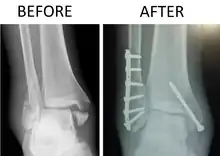

| X-ray of trimalleolar fracture repair before and after ORIF surgery | |

A trimalleolar fracture is a fracture of the ankle that involves the lateral malleolus, the medial malleolus, and the distal posterior aspect of the tibia, which can be termed the posterior malleolus. The trauma is sometimes accompanied by ligament damage and dislocation.[1]

Surgical repair using open reduction and internal fixation is generally required, and because there is no lateral restraint of the foot, the ankle cannot bear any weight while the bone knits. This typically takes six weeks in an otherwise healthy person, but can take as much as twelve weeks. Non-surgical treatment may sometimes be considered in cases where the patient has significant health problems or where the risk of surgery may be too great.[1]